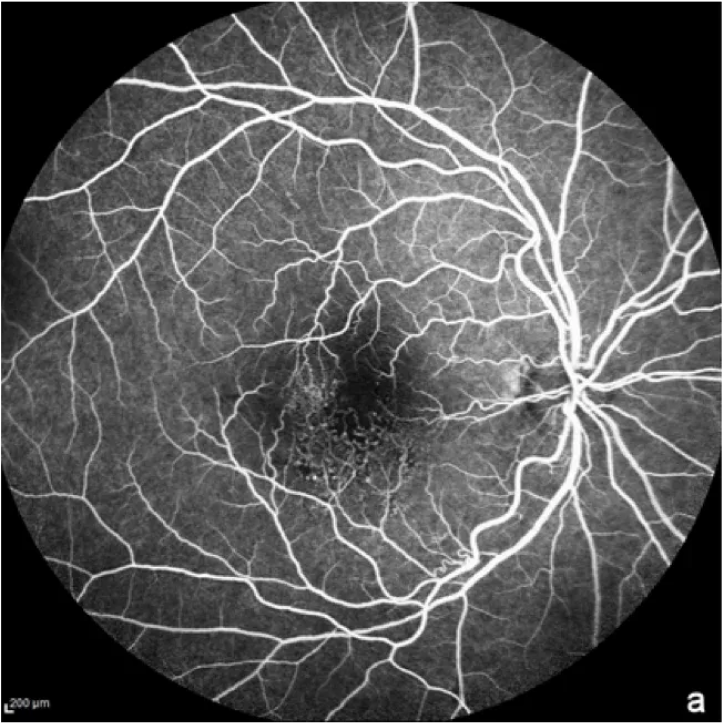

Angiografia de fundo ocular com fluoresceína (FFA)

Nesse exame, um contraste fluorescente é injetado na veia para visualizar os vasos sanguíneos da retina. A FFA geralmente é usada para descartar um diagnóstico de DMRI úmida.1 Também pode ser usada na atrofia geográfica para mostrar as regiões com danos onde as células da retina morreram.7

Autofluorescência do fundo ocular

A autofluorescência do fundo de olho é uma técnica de imagem importante para o diagnóstico e o monitoramento da DMRI, particularmente de uma de suas formas avançadas, a atrofia geográfica.1 Quando exposta a uma luz específica (normalmente azul), uma molécula no olho chamada lipofuscina produz luz, ou fluorescência, que pode ser observada. Regiões não saudáveis podem parecer mais escuras para áreas atróficas, ou mais brilhantes para drusas, que são sinais de DMRI.7